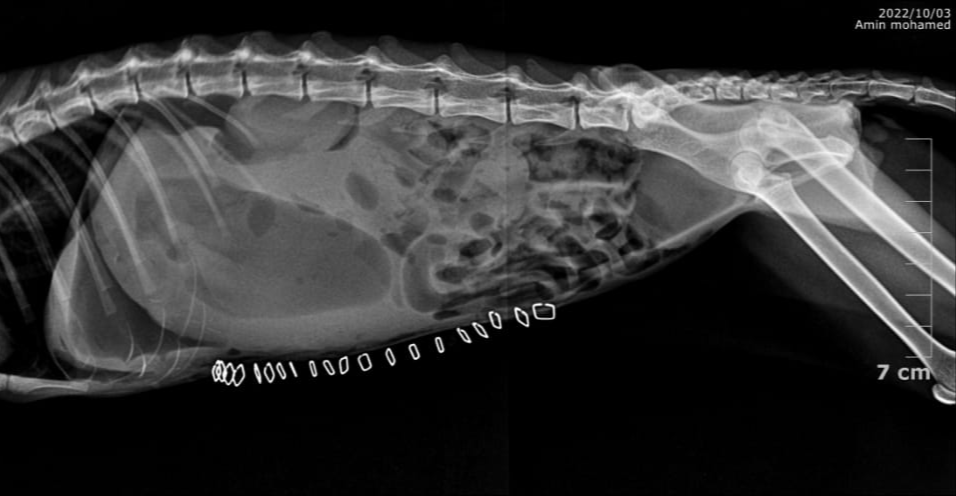

years old cat with fb lodged between the antrum and duodenum

Fluid filled stomach due to duodenal obstruction causing improper emptying

Gastric distension due to fluid accumulation